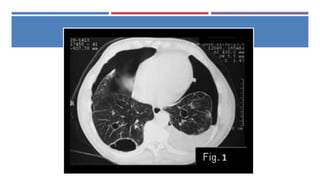

DIAGNÓSTICO

 Clínica

 Rx PA de tórax y lateral

 TAC: útil cuando el tamaño del

neumotórax es menor a 15% del

hemitórax afectado